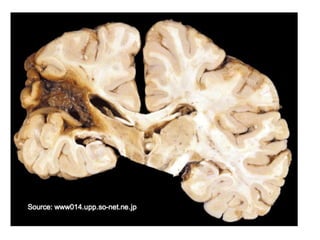

Necrosis licuefactiva

Se observa en infecciones bacterianas o

reacciones inflamatorias intensas. Presencia

de pus.

En hipoxia del SNC

Hay digestión de las células muertas,

transformando el tejido en una masa viscosa

líquida.

Necrosis de licuefacción. Infarto Cerebral